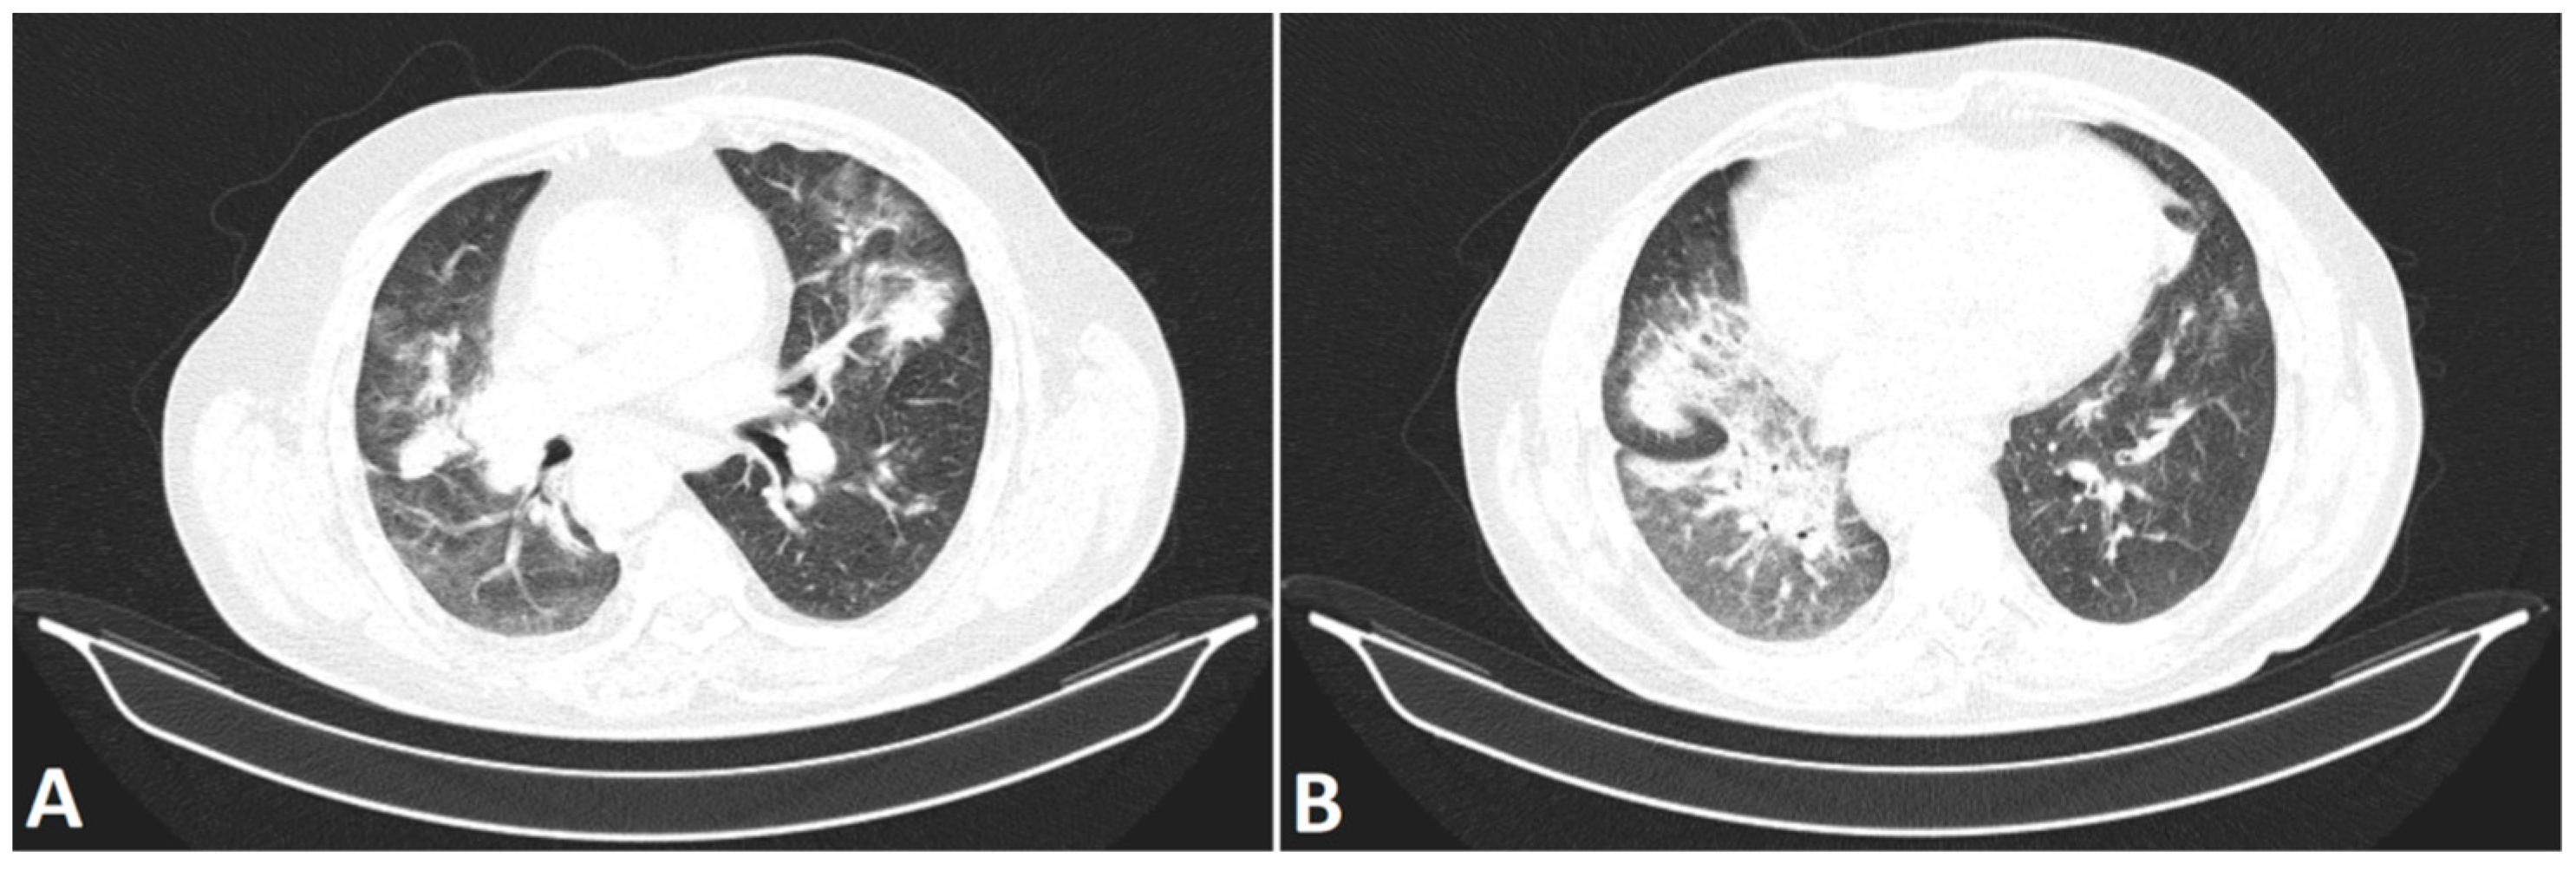

- Mostafavi, S.M. COVID19-CT-Dataset: An Open-Access Chest CT Image Repository of 1000+ Patients with Confirmed COVID-19 Diagnosis 2021. Available online: https://doi.org/10.7910/DVN/6ACUZJ (accessed on 21 June 2022).

- Yan, T. COVID-19 and Common Pneumonia Chest CT Dataset (416 COVID-19 Positive CT Scans). 2020, Volume 2. Available online: https://doi.org/10.17632/3y55vgckg6.2 (accessed on 21 June 2022).

- Franquet, T. Imaging of pulmonary viral pneumonia. Radiology 2011, 260, 18–39. [Google Scholar] [CrossRef] [PubMed]

- Raharja, S.; Hussein, S. Radiographic development and resolution of lung abscess. Br. J. Hosp. Med. Lond. Engl. 2020, 81. [Google Scholar] [CrossRef]

- Choh, N.A.; Parry, A.H.; Wani, A.H.; Feroz, I.; Bhat, M.H.; Shaheen, F.A. The spectrum of imaging findings in pulmonary hydatid disease and the additive value of T2-weighted magnetic resonance imaging in its diagnosis. Pol. J. Radiol. 2021, 86, e53–e63. [Google Scholar] [CrossRef]

- Skoura, E.; Zumla, A.; Bomanji, J. Imaging in tuberculosis. Int. J. Infect. Dis. Off. Publ. Int. Soc. Infect. Dis. 2015, 32, 87–93. [Google Scholar] [CrossRef] [Green Version]

- Kunihiro, Y.; Kobayashi, T.; Tanaka, N.; Matsumoto, T.; Okada, M.; Kamiya, M.; Ueda, K.; Kawano, H.; Matsunaga, N. High-resolution CT findings of primary lung cancer with cavitation: A comparison between adenocarcinoma and squamous cell carcinoma. Clin. Radiol. 2016, 71, 1126–1131. [Google Scholar] [CrossRef]

- Seo, J.B.; Im, J.G.; Goo, J.M.; Chung, M.J.; Kim, M.Y. Atypical pulmonary metastases: Spectrum of radiologic findings. Radiogr. Rev. Publ. Radiol. Soc. N. Am. Inc 2001, 21, 403–417. [Google Scholar] [CrossRef] [PubMed]

- Yan, T. COVID-19 and Common Pneumonia Chest CT Dataset (412 Common Pneumonia CT Scans). 2020, Volume 1. Available online: https://doi.org/10.17632/ygvgkdbmvt.1 (accessed on 21 June 2022).

- Li, P.; Wang, S.; Li, T.; Lu, J.; HuangFu, Y.; Wang, D. A Large-Scale CT and PET/CT Dataset for Lung Cancer Diagnosis 2020. Available online: https://doi.org/10.7937/TCIA.2020.NNC2-0461 (accessed on 21 June 2022).